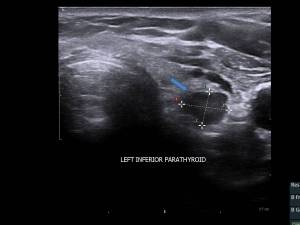

Having had a couple of ultrasounds recently, I’ve come to the conclusion that radiologists’ minds aren’t right. I mean, just look at this schematic:

Anyway, my radiologist yesterday saw “something” in the region of my left inferior parathyroid gland, but it didn’t look like the second image above. I knew there was something going on when she spent about ten minutes pressing and probing the same area, asking me to swallow, more pressing and probing. All in silence. She was very good, went over the background of what she was looking for and explaining what was what. She told me there was something there, but it’s atypical of an adenoma, it might be something on or near or associated with my oesophagus. She’s going to consult with her colleague and probably organise different imaging to have a look at it. It’s probably an undiagnosed siamese twin. Or a tumour.